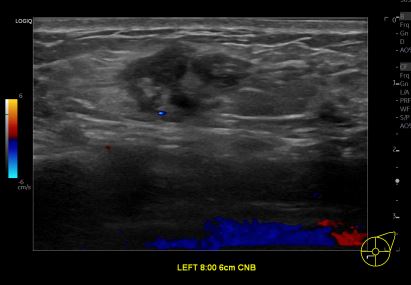

상기환자는 외부검사 이상소견으로 내원하신 30대후반 여성분으로 의심스러운 좌측 혹 조직검사 시행해 유방암 진단되었습니다.